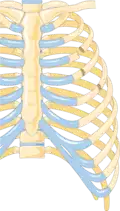

Illustration showing rib fracture at 3rd, 4th and 5th rib -